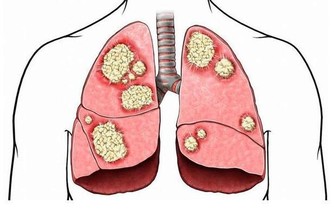

提高患癌風險

熬夜會讓內分泌激素水平紊亂,使得細胞代謝異常,影響人體細胞正常分裂,導致細胞突變,提高患癌風險。